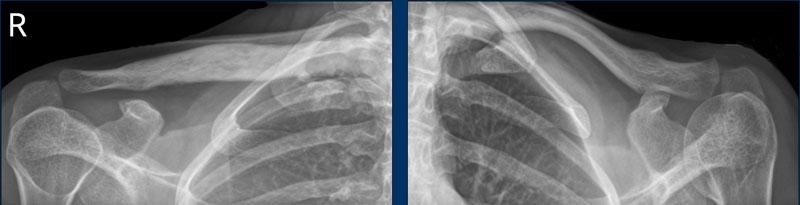

Bào mòn xương lớn tại đầu trên xương cánh tay, ổ chảo và mỏm cùng vai ở bệnh nhân viêm khớp tự phát thiếu niên.

Bào mòn xương và hẹp khe khớp háng phải ở bệnh nhân viêm khớp tự phát thiếu niên.